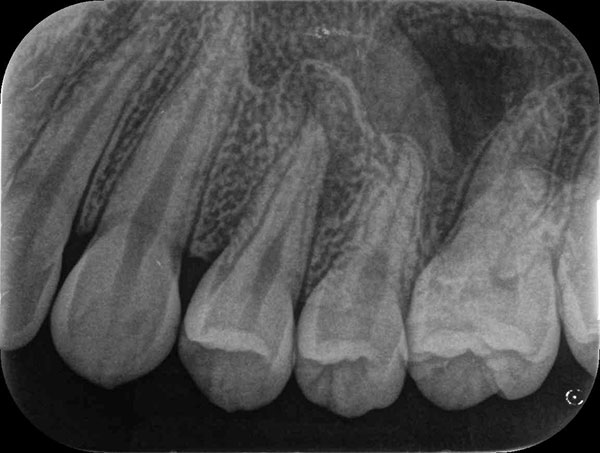

術前

術後

症例について

主訴:

硬いものを食べると違和感があり疲れたら歯が浮いてる様な感じがする

治療内容:

過去に行った根管治療をやり直し、再感染の原因を取り除く治療です。

治療期間:各90分 2回

費用:クラウンコア除去 5,500円(税込)/ 隔壁形成 5,500円(税込)/ 再根管治療 132,000円(税込)/ 築造 16,500円(税込)

治療に関わるリスクまたは副作用:

症状が改善しない場合、外科的歯内療法または抜歯が必要になることがあります。